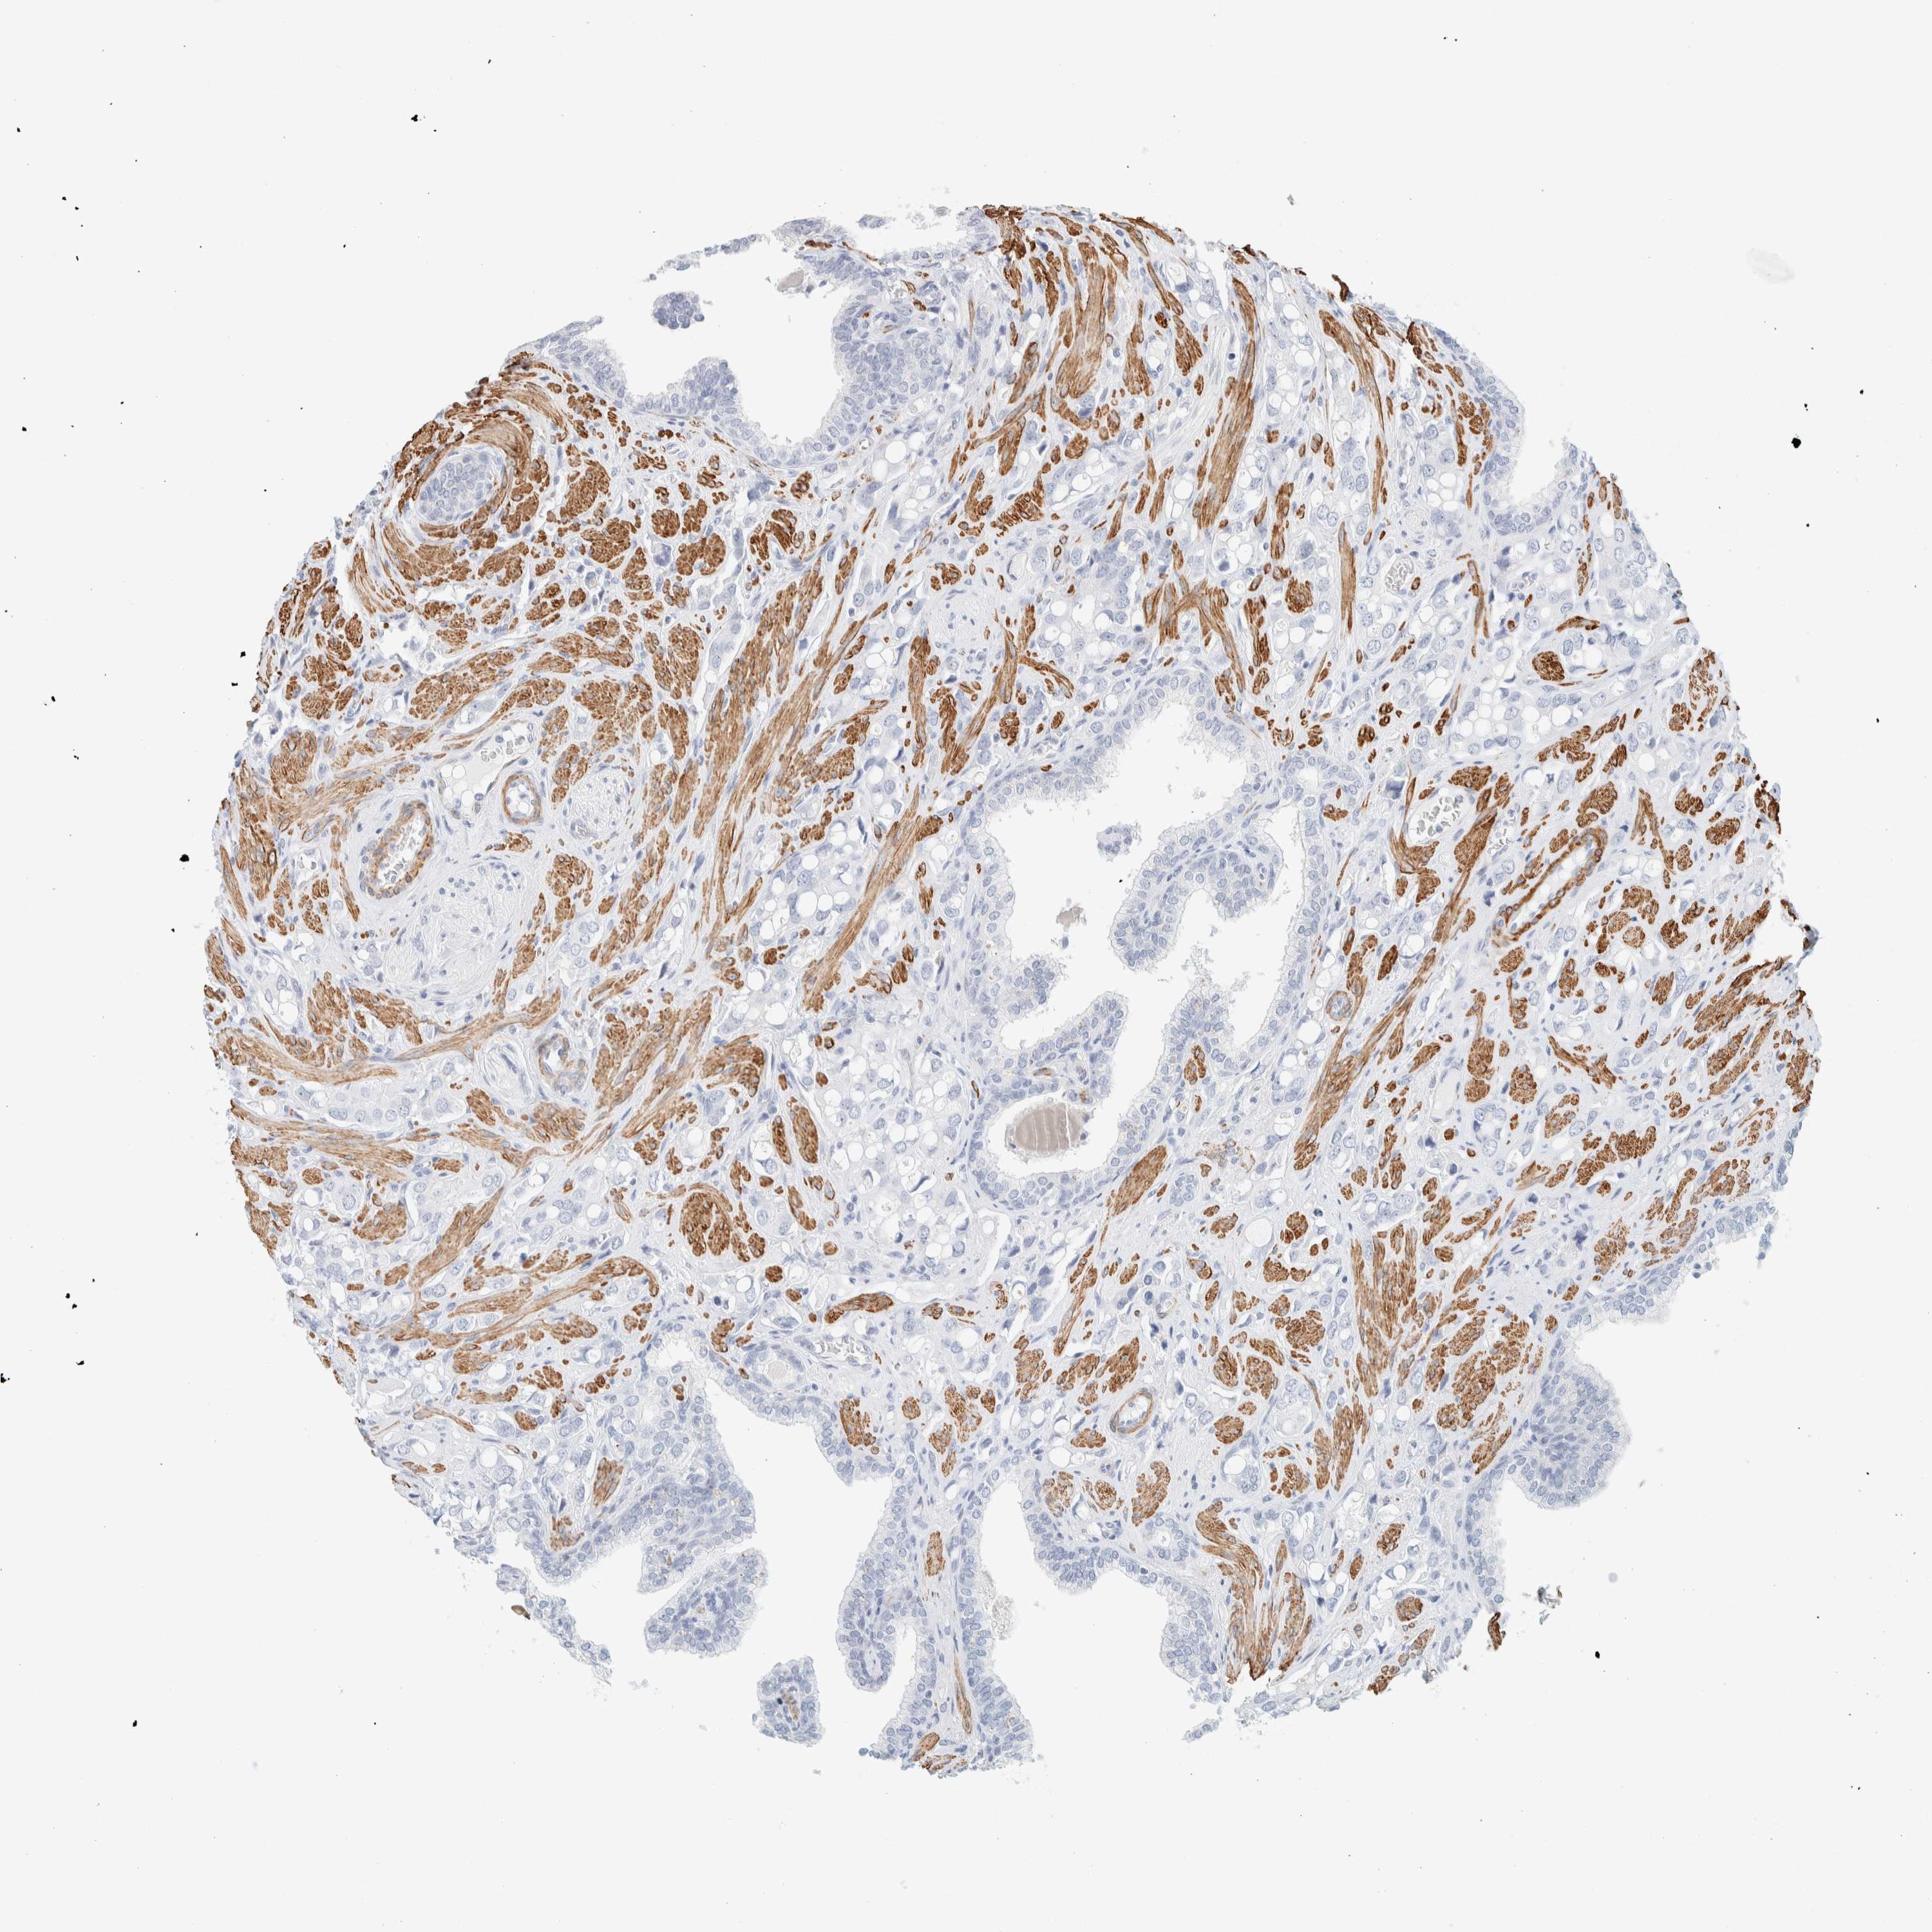

PROSTATE CANCER - Protein expressioni

A mouse-over function shows sample information and annotation data. Click on an image to view it in a full screen mode. Samples can be filtered based on level of antibody staining by selecting one or several of the following categories: high, medium, low and not detected. The assay and annotation is described here.

Note that samples used for immunohistochemistry by the Human Protein Atlas do not correspond to samples in the TCGA dataset.

Antibody stainingi

Antibody staining in the annotated cell types in the current human tissue is reported as not detected, low, medium, or high, based on conventional immunohistochemistry profiling in selected tissues. This score is based on the combination of the staining intensity and fraction of stained cells.

Each image is clickable and will lead to virtual microscopy that enables deeper exploration of all samples and also displays staining intensity scores, fraction scores and subcellular localization as well as patient and tissue information for each sample.

Antibody HPA023861

Antibody HPA026536

Staining

High

Medium

Low

Not detected

Intensity

Strong

Moderate

Weak

Negative

Quantity

>75%

75%-25%

<25%

None

Location

Nuclear

Cytoplasmic/membranous

Cytoplasmic/membranous,nuclear

Adenocarcinoma, High grade

Adenocarcinoma, Low grade